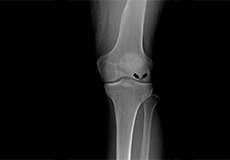

Knee Fracture Surgery

A knee fracture is a broken bone or a crack in or around the joint of the knee. This can involve the tibia (shin bone), the kneecap (patella), or femur (thighbone) where they connect with the knee.